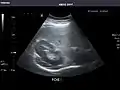

Abdominal ultrasound can be used to diagnose abnormalities in various internal organs, such as the kidneys,[1] liver, gallbladder, pancreas, spleen and abdominal aorta. If Doppler ultrasonography is added, the blood flow inside blood vessels can be evaluated as well (for example, to look for renal artery stenosis). It is commonly used to examine the uterus and fetus during pregnancy; this is called obstetric ultrasonography.[2][3]

Ultrasonography of the kidneys is essential in the diagnosis and management of kidney-related diseases. The kidneys are easily examined, and most pathological changes in the kidneys are distinguishable with ultrasound.[7]

Kidneys: Right and left kidneys measure 11.5 cm and 12 cm in length respectively. No hydronephrosis. Small left lower pole kidney cyst.